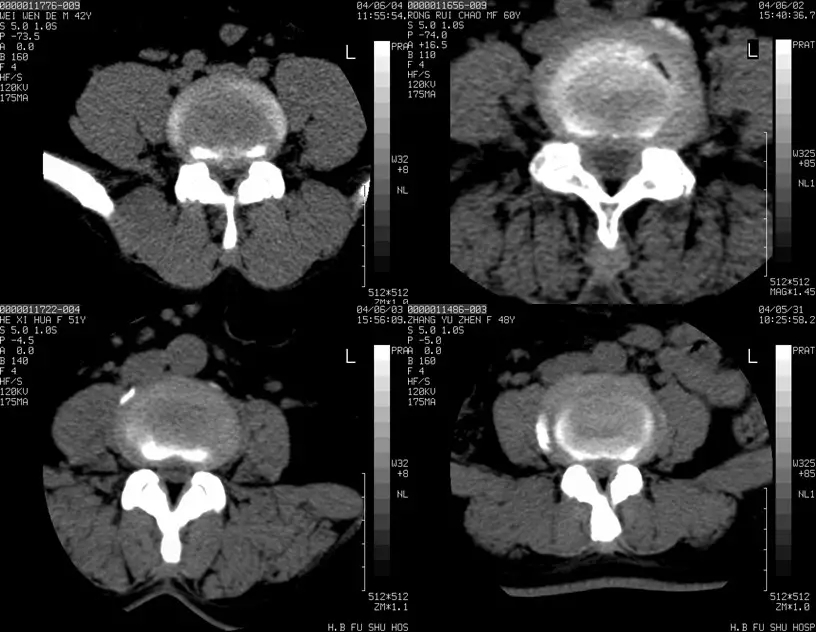

椎间盘突出的CT表现

直接征象:A、椎间盘后缘向椎管内局限性突出,密度与相应椎间盘一致,形态不一。B、突出的椎间盘可有大小、形态不一的钙化,多与椎间盘相连;C、椎管内硬膜外可见髓核游离碎片,密度高于硬膜囊;D、许莫结节表现为椎体上(下)缘边缘清楚的隐窝状压迹,多位于椎体中后1/3交界部,常上下对称出现。其中心密度低,为突出的髓核及软骨板,外周为反应性骨硬化带。

间接征象:A、硬膜外脂肪间隙变窄、移位、或消失。B、硬膜囊前缘或侧方及神经根受压移位。C、周围骨结构改变,突出髓核周围骨质硬化。

正常椎间盘CT图像

椎间盘突出图像

椎间盘突出(中央型)

中央型

椎间盘突出右旁中央型

椎间盘突出左旁中央型